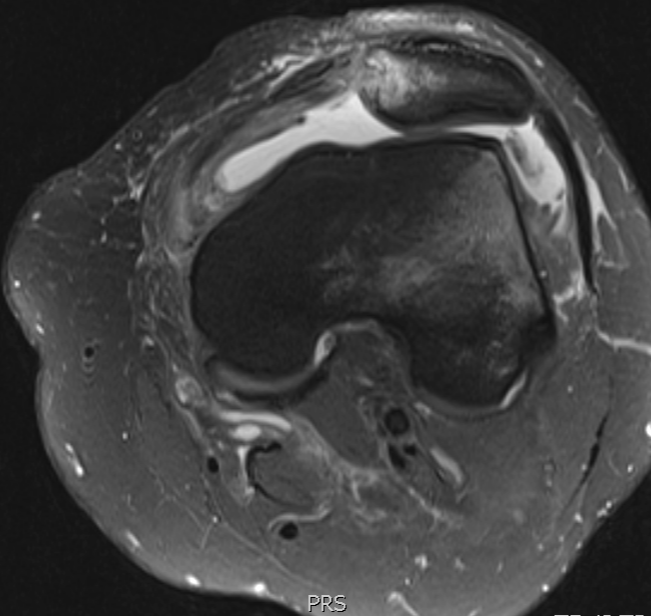

3. Transient patellar dislocation